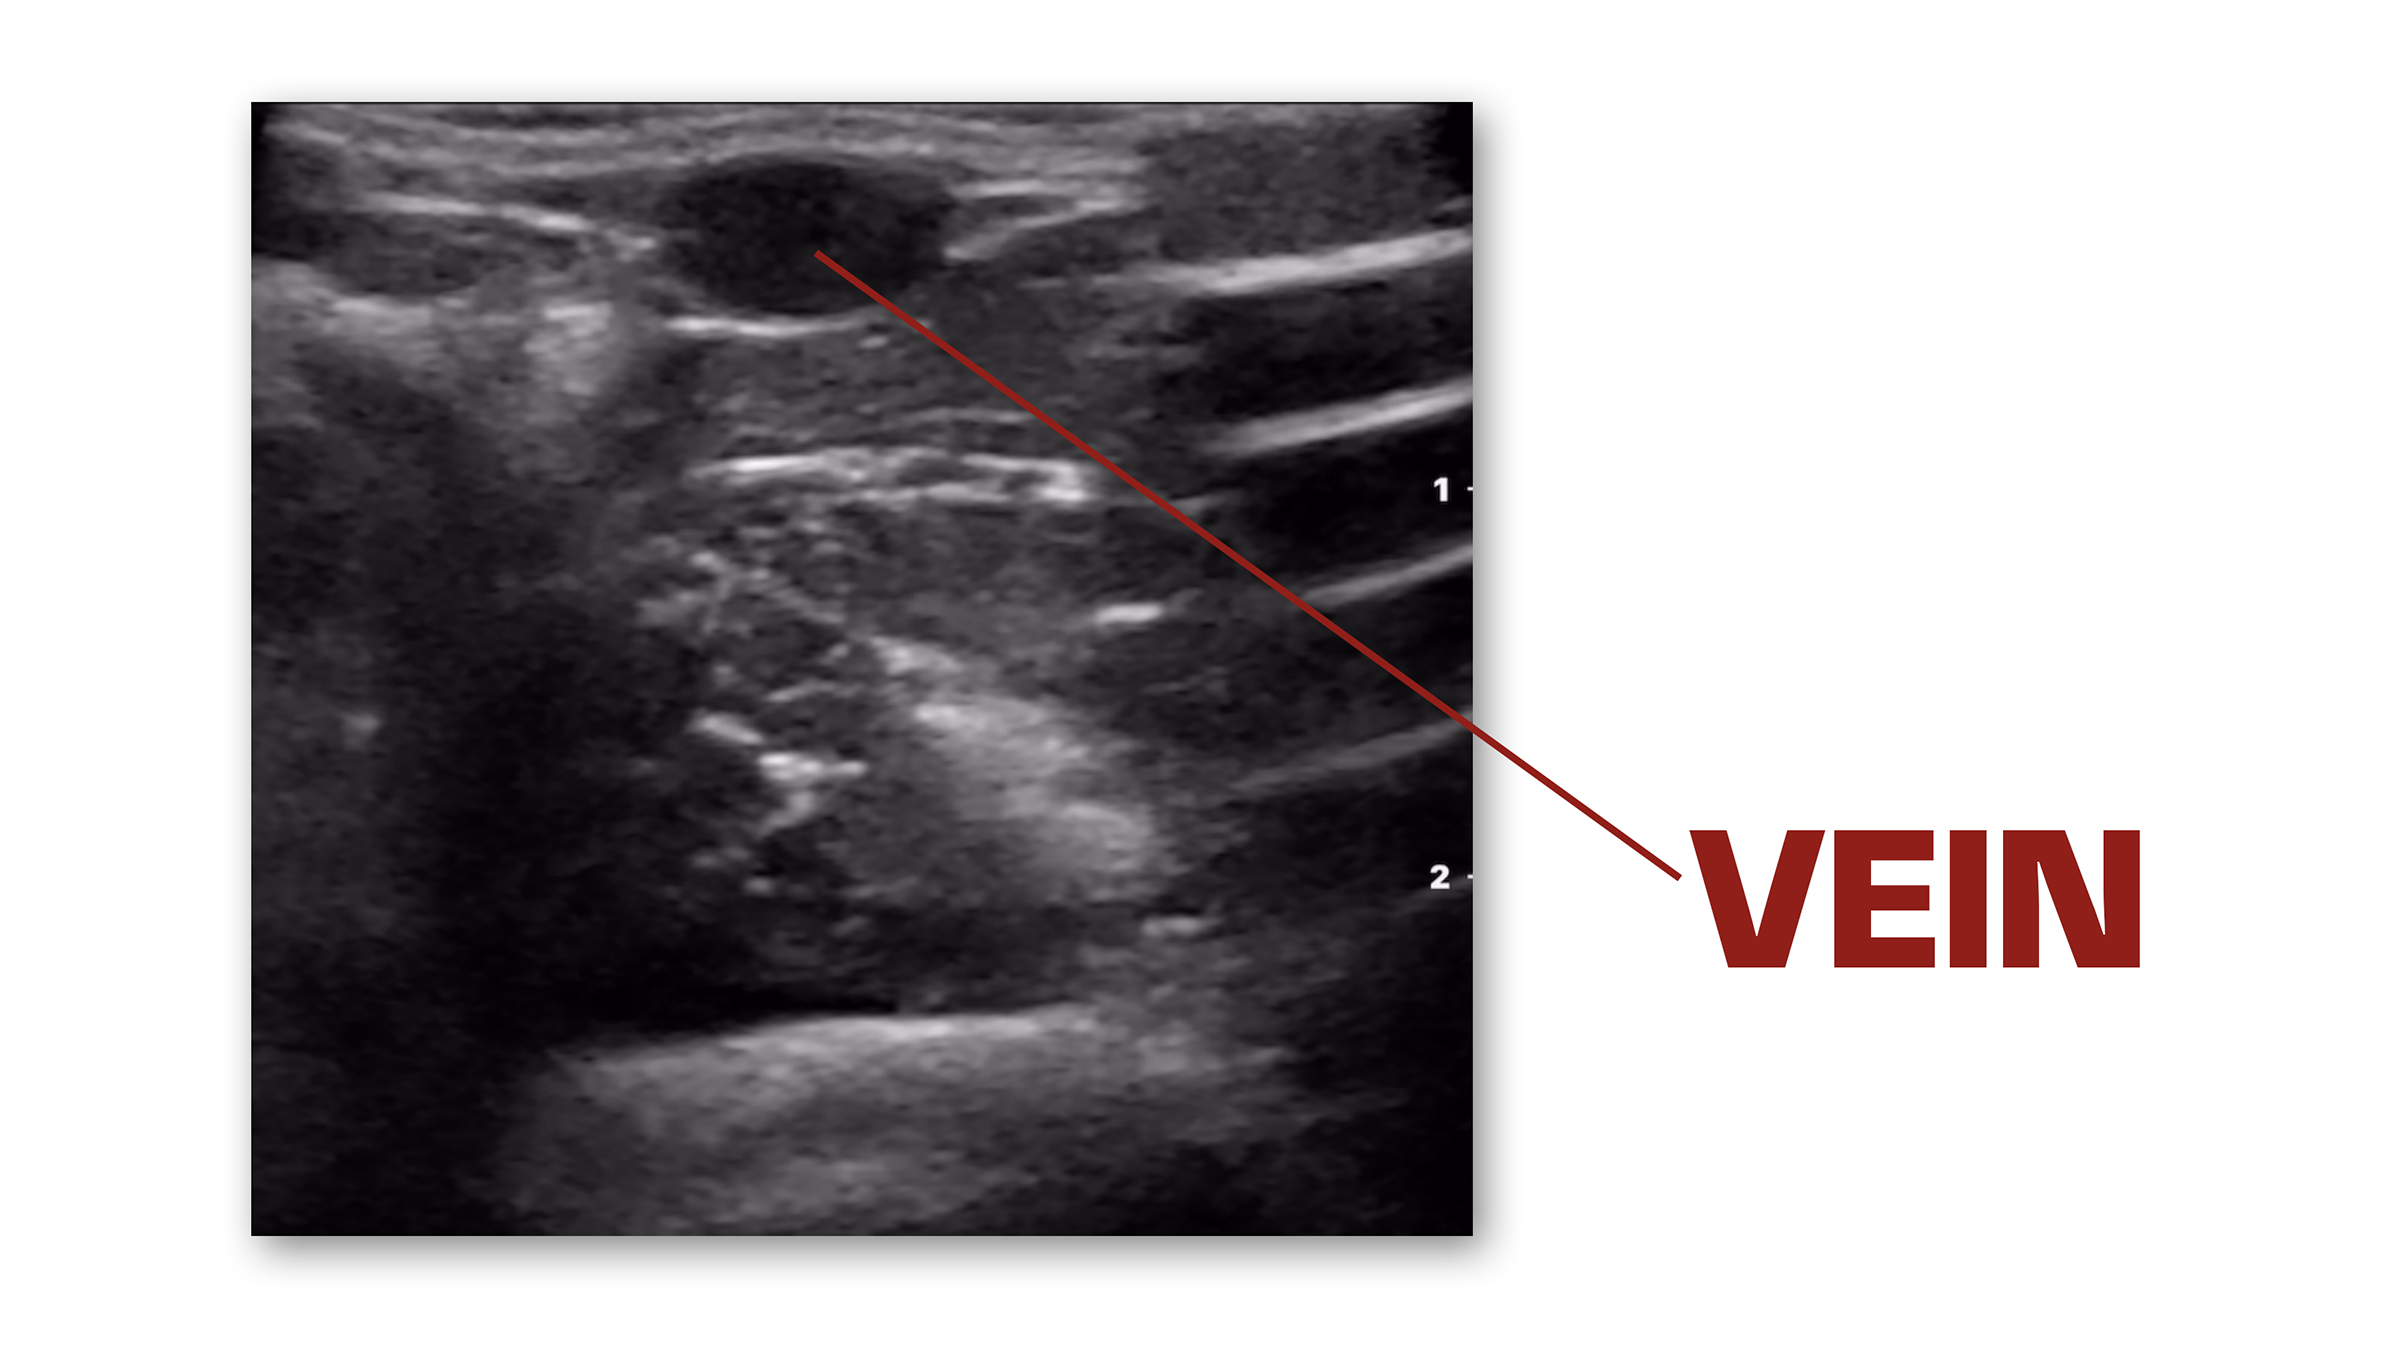

So let's talk about vascular access. This is one of the great things that you can do with ultrasound. I'm using the Butterfly IQ 3 plugged into my iPhone here. First thing I'm going to do is go to presets and make sure I'm on vascular access. I'm going to select that, and as you can see, if I place it over a vessel. Right there. I've got it over that vein, and you can see that dark circle. And then the other thing that you can do is gently press down on it, and you'll see that vein easily compresses. So now I know I'm right over a vein and I've got a transverse view of it.